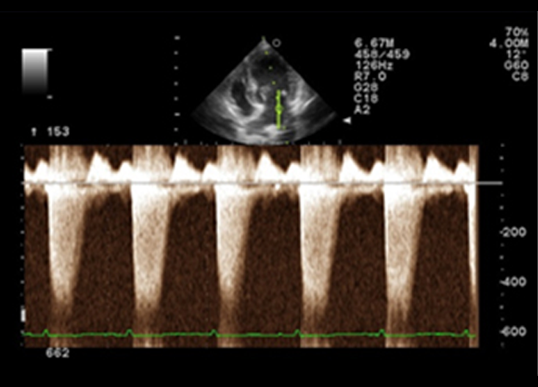

심장초음파(Echocardioagraphy) 검사

심장초음파를 통해 심장과 대혈관의 질환을 진단할 수 있는 검사법입니다. 심장초음파 검사는 심장 검사용 탐촉자를 이용하여 기본 영상과 도플러 검사를 통해 심장과 혈류의 움직임을 실시간으로 평가하고, 심근의 기능을 평가할 수 있는 검사입니다. 이를 통해 이첨판 폐쇄부전, 삼첨판 폐쇄부전, 동맥관 개존증(PDA), 폐고혈압과, 폐동맥 협착증, 대동맥 협착증과 같은 심장과 대혈관 질병을 진단하고 치료 경과의 확인을 위해 주기적인 재검사를 실시하고 있습니다.